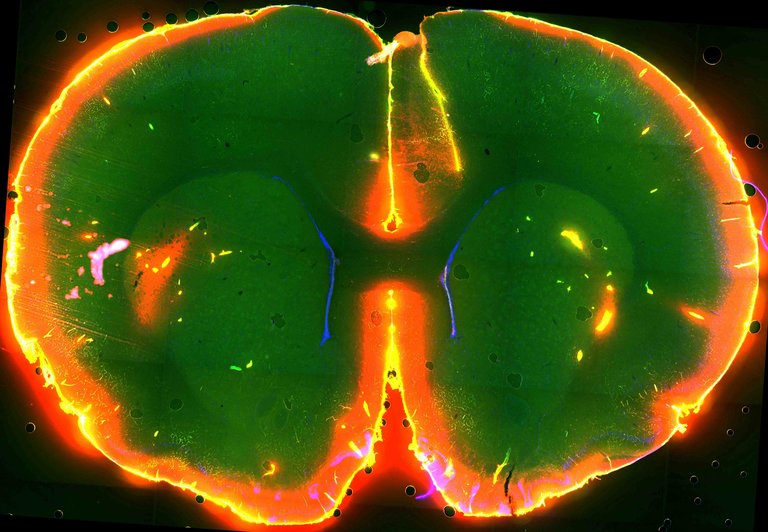

Zelulen artean mugitzen den fluidoak eramaten du garunean pilatzen den zaborra zirkulazio-sistema orokorrera, hark, gero, gibelera eramateko. Ikertzaileek bazuten susmoa garbiketa-prozesu hori gaueko lan bat izan zitekeela; energia dezente xahutzen duenez, garuna esna dagoenean egin beharreko beste lan guztiekin bateragarria izango ez zelakoan. Gaur Sciencen argitaratu duten ikerketan baieztatu dute hori hala dela. Ikusi dute sistema askoz ere aktiboagoa dela saguak lo daudenean. Hain zuzen, lo daudenean kanporatzen duten zaborraren % 5 baino ez dute kanporatzen esna daudenean. Gainera, lo daudenean garuneko zelulak txikitu egiten direla ere ikusi dute, eta, ondorioz, zelulen arteko espazioa % 60 handitzen dela. Horrek garbiketa-sistema eraginkorragoa egiten du.

Ikertzaileek nabarmendu dute garbiketa-sistema horrek nola funtzionatzen duen jakitea garrantzitsua dela, garunean pilatzen den zaborrarekin lotura baitute hainbat gaixotasunek. Alzheimerra, esaterako, β-amiloideen pilaketarekin lotuta dago, eta ikerketa honetan jarraipena egin diote molekula horri. Ikusi dute saguak lo daudenean bi aldiz azkarrago kanporatzen direla β-amiloideak.